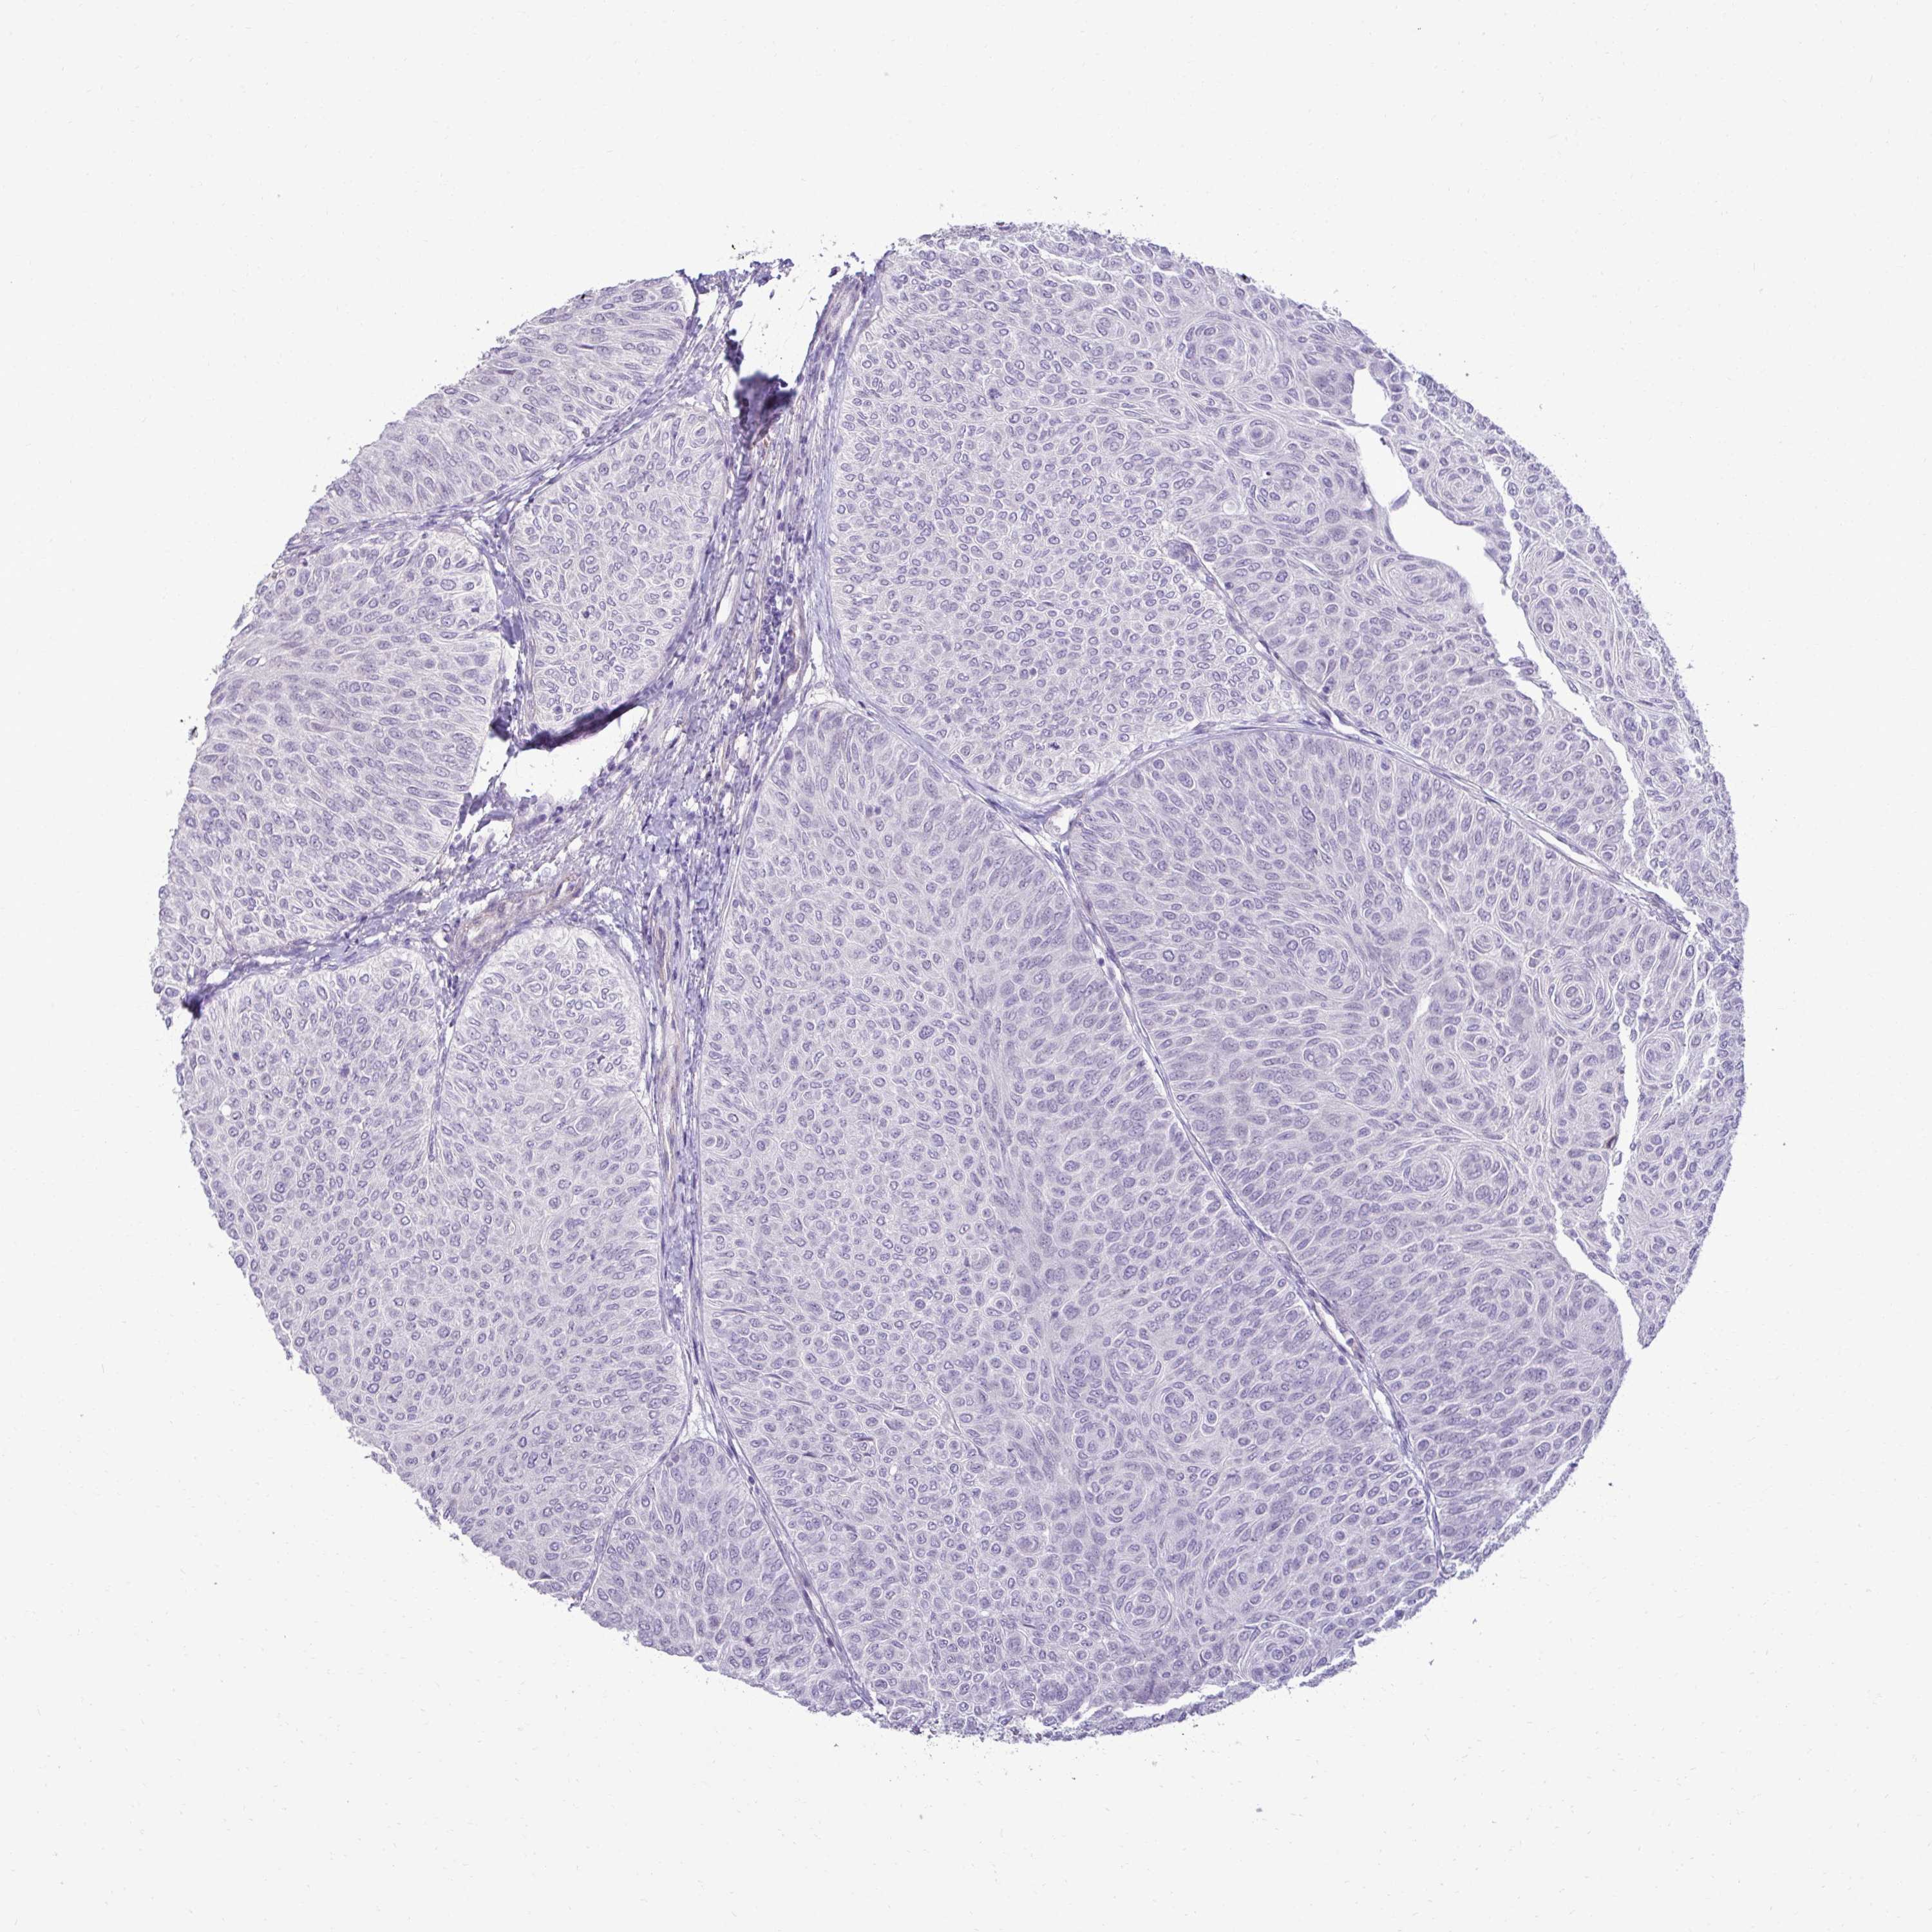

UROTHELIAL CANCER - Protein expressioni

A mouse-over function shows sample information and annotation data. Click on an image to view it in a full screen mode. Samples can be filtered based on level of antibody staining by selecting one or several of the following categories: high, medium, low and not detected. The assay and annotation is described here.

Antibody stainingi

Antibody staining in the annotated cell types in the current human tissue is reported as not detected, low, medium, or high, based on conventional immunohistochemistry profiling in selected tissues. This score is based on the combination of the staining intensity and fraction of stained cells.

Each image is clickable and will lead to virtual microscopy that enables deeper exploration of all samples and also displays staining intensity scores, fraction scores and subcellular localization as well as patient and tissue information for each sample.

Antibody HPA060505

Antibody HPA067637

Urothelial carcinoma, High grade

Urothelial carcinoma, Low grade

Urothelial carcinoma, NOS